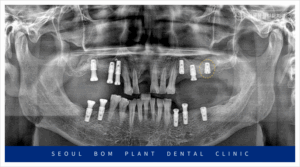

먼저 왼쪽 위턱의

기존 상실된 부위부터

임플란트 식립을 진행하였으며

잇몸이 아무는 정도에 따라

아래턱 오른쪽과 왼쪽에 차례대로

임플란트 식립을 진행하였는데요.

발치를 했던 부위이다 보니

잔존 치조골의 양이 부족하여

잇몸뼈를 충분히 보완한 뒤

안정적으로 임플란트 식립을

도와드렸습니다.

위턱의 오른쪽 임플란트도 진행하였는데요.

위턱 오른쪽 어금니 부위의 경우

잔존 치조골과 상악동과의 거리가

가깝게 위치해 있어

임플란트를 식립하기에는

수직적인 거리가 부족하여

이 경우 상악동 거상술을 동반한

뼈이식이 필요하였는데요.